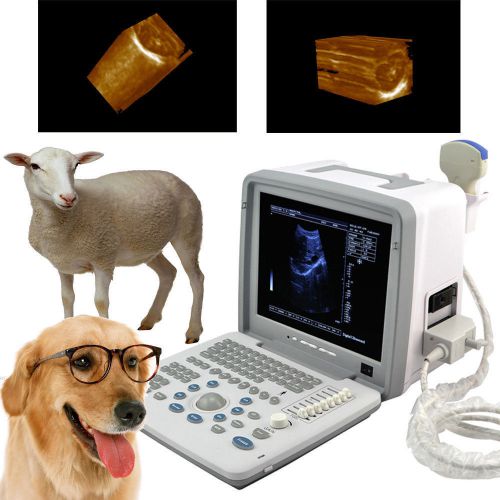

Brand | Denshine |

| Screen | 12-inch SVGA high resolution monitor | ||

| technology | Full digital imaging technology | ||

| Probes optional | convex linear transvaginal rectal | ||

| probe connectors | two | ||

| Approved | CE FDA | ||

| 3D | 3D Ultrasound image working station |

Veterinary VET 3D Full Digital Portable Ultrasound Scanner convex 3D workstation